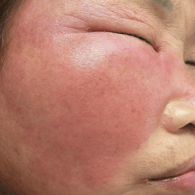

Absceso facial

Un absceso facial es una acumulación de pus en los tejidos faciales debido a una infección bacteriana.

Los pacientes pueden notar hinchazón, dolor intenso, fiebre y enrojecimiento en el área afectada.

El tratamiento incluye el drenaje quirúrgico del absceso y el uso de antibióticos para combatir la infección.